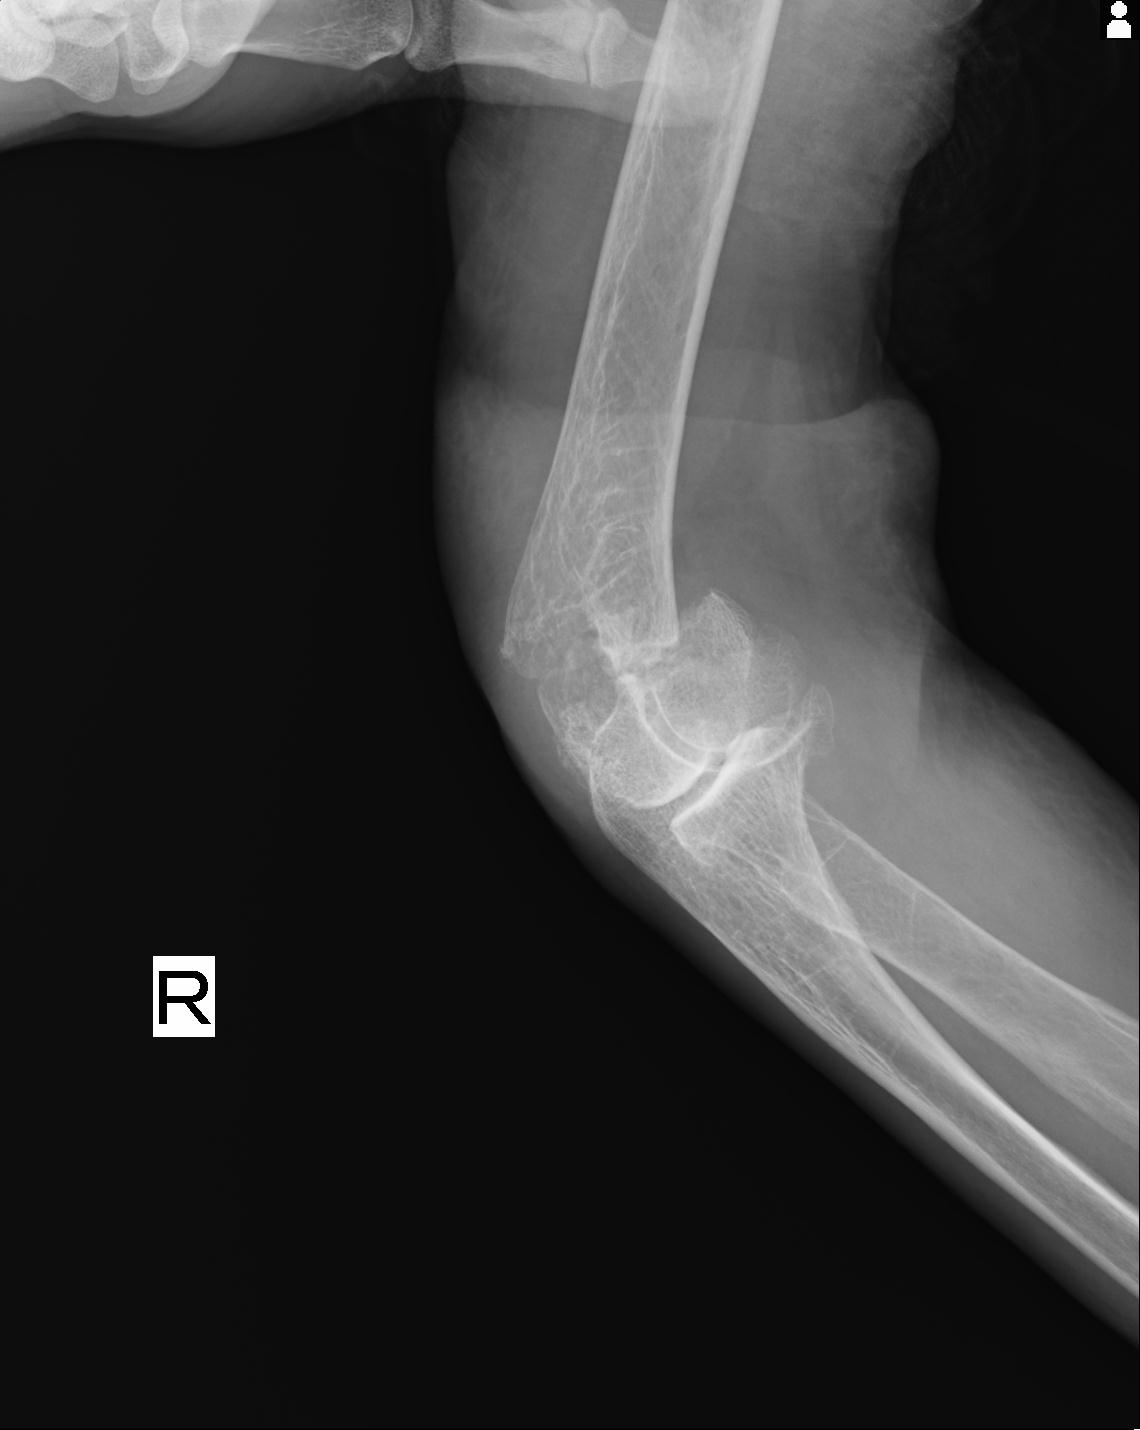

2271 1/25 右肘 4R 1/27 4R 3/24 4R 94歳女性 右通顆骨折